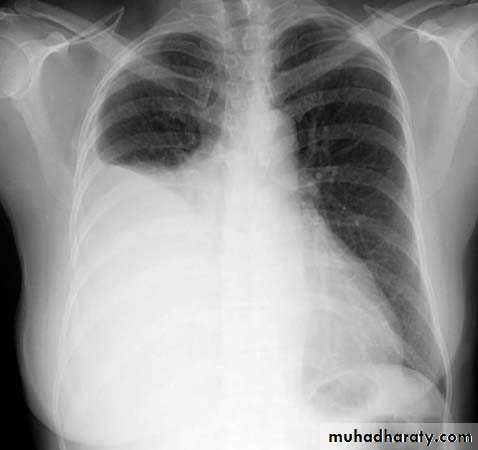

Pleural effusion

50.pleural effusion

51.pleural effusion .